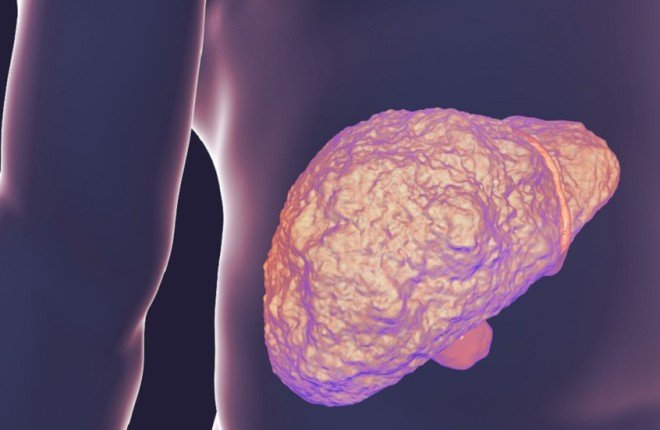

كشفت دراسة علمية حديثة أن بلورات الكوليسترول المتراكمة داخل الكبد قد تؤدي إلى تصلّبه في مراحل مبكرة لدى المصابين بمرض الكبد الدهني المرتبط باضطراب التمثيل الغذائي (MASLD)، وذلك قبل ظهور التندّب بفترة طويلة، ما يفتح الباب أمام فرص جديدة للتشخيص والتدخل العلاجي المبكر.

يحدث MASLD نتيجة تراكم الدهون الزائدة في الكبد، وغالبًا ما يرتبط بالسمنة، ومقاومة الأنسولين، وداء السكري من النوع الثاني، إضافة إلى سوء التغذية والعوامل الوراثية. وفي بعض الحالات المتقدمة، قد يتطور المرض إلى تليّف الكبد أو سرطان الكبد، وقد يستدعي زراعة كبد.

أظهرت النتائج أن بلورات الكوليسترول لا تسهم فقط في تصلّب أنسجة الكبد، بل تخلق بيئة مهيأة لزيادة التندّب. وتمكن الباحثون من عكس تصلب الكبد لدى الفئران عبر إزالة هذه البلورات، غير أن هذه الآلية لم تُختبر بعد على البشر.